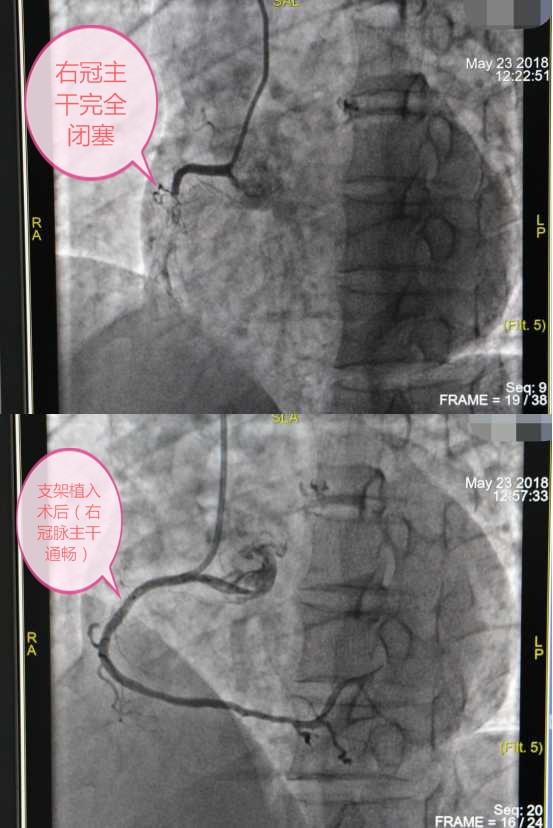

当病人已经发生心梗,能否最快时间开通梗阻的血管,是挽救生命健康的关键。马军在医生的安排下,在该院介入中心做进一步检查,经冠脉造影检查很快便找到了病变部位:冠心病RCA闭塞性病变。

该院特聘国药东风总医院心血管学科带头人闵新文教授与该院急危重症医学科主任严文军、心内科主任周三军根据屏幕上的造影结果进行现场分析,显示血管完全闭塞,这种情况需继续进行介入治疗,经充分与患者及家属进行沟通同意后,决定为他植入支架,方能保持冠状动脉管腔的开放,降低心梗再次发生率。

手术台上,专家们身披重达十余斤铅制围脖、铅衣,准备工作完毕后开始进行介入治疗,经过一个小时,两枚支架成功植入了冠脉,造影显示RCA病变消失,术后,患者立感胸闷减轻,仿佛获得了“重生”。

图上:右冠主干完全闭塞;图下:支架植入术后(右冠脉主干通畅)